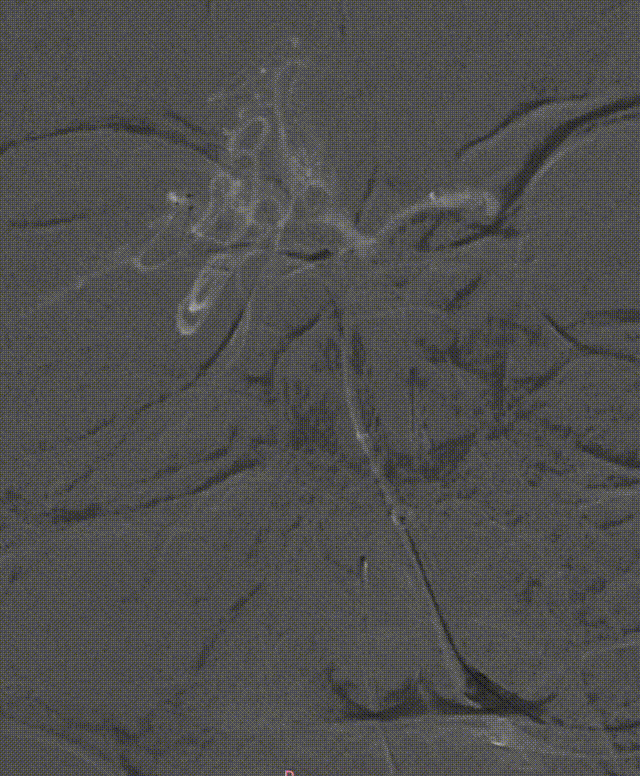

左侧大脑后动脉P1段发白,观察20min较前好转,血流状态维持良好,结束手术。